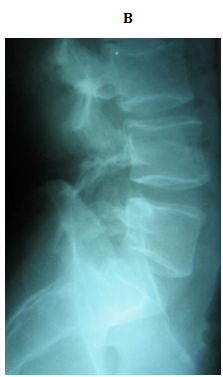

No implant failure was detected in the follow up radiographs. At the final follow up, radiological healing could be achieved bilaterally in all patients (86.6%) but four. Three of them had initial defects >3mm and one from 2-3mm, all at L5. For the healed cases, the mean time to union was 4.7 months. In the cases which did not heal, only 1 complained of significant back pain at final follow up. The other 3 did not complain of pain at final follow up (Figures 3 & 4).

Figure 4 A 23 years old female with double level spodylolyis at L4 and L5. (A, B) Preoperative plain radiographs. (C,D) 3 months after direct pars repair with cable screw construct at both levels.